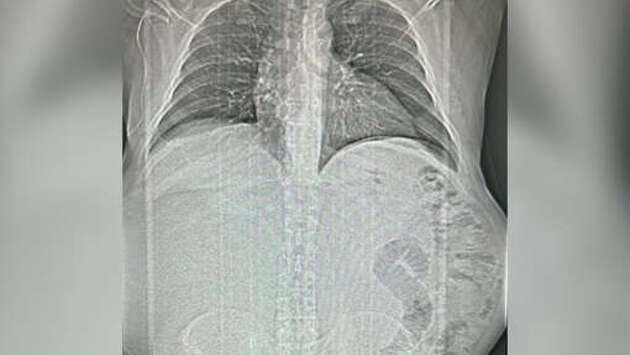

Врачи Краевой rлинической больницы N1 имени профессора С.В. Очаповского спасли пациента, удалив ему гигантскую опухоль. Об этом министр здравоохранения Краснодарского края Евгений Филиппов сообщил в своем Telegram-канале. Как рассказал глава ведомства, пациент активно болел около года - он стремительно набирал вес, но не обращался за помощью, так как развивавшееся образование не мешало жить. Во время диагностики медики нашли у пациента объемное новообразование в брюшной полости. Операция по удалению новообразования длилась четыре часа. Вес опухоли составил около 17 килограммов. "Ювелирная работа специалистов не только спасла жизнь человека, но и в очередной раз доказала, как важно вовремя обращаться за помощью к врачам", - подчеркнул Филиппов.